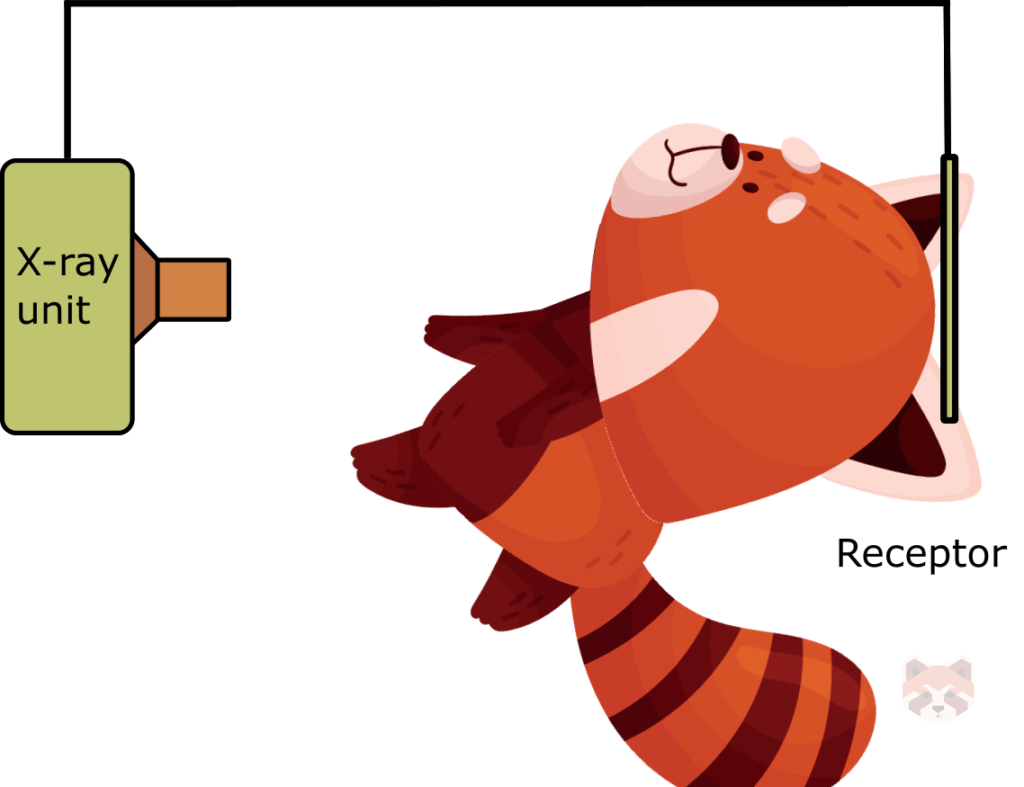

The most commonly used and preferred (most accurate) radiographic technique is the paralleling technique, where the film is held parallel to the long axis of the tooth, producing the most accurate 2D representation of the object. However this is not always possible, likely due to anatomical restrictions. The bisecting angle technique is used as a compromise, where the central ray is oriented perpendicular to the bisecting line made from the angle of the film to the object. Using this technique will keep distortion to a minimum.